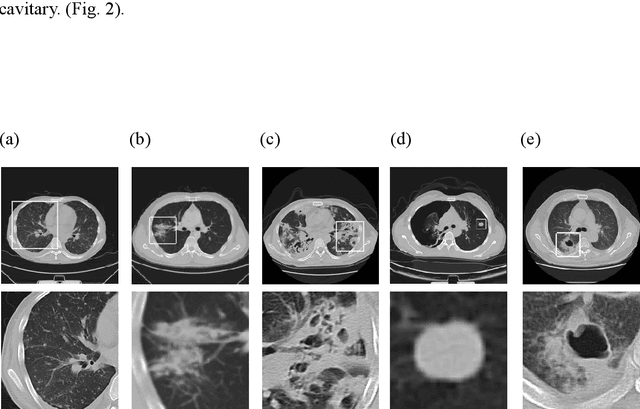

Abstract:We developed a deep learning model-based system to automatically generate a quantitative Computed Tomography (CT) diagnostic report for Pulmonary Tuberculosis (PTB) cases.501 CT imaging datasets from 223 patients with active PTB were collected, and another 501 cases from a healthy population served as negative samples.2884 lesions of PTB were carefully labeled and classified manually by professional radiologists.Three state-of-the-art 3D convolution neural network (CNN) models were trained and evaluated in the inspection of PTB CT images. Transfer learning method was also utilized during this process. The best model was selected to annotate the spatial location of lesions and classify them into miliary, infiltrative, caseous, tuberculoma and cavitary types simultaneously.Then the Noisy-Or Bayesian function was used to generate an overall infection probability.Finally, a quantitative diagnostic report was exported.The results showed that the recall and precision rates, from the perspective of a single lesion region of PTB, were 85.9% and 89.2% respectively. The overall recall and precision rates,from the perspective of one PTB case, were 98.7% and 93.7%, respectively. Moreover, the precision rate of the PTB lesion type classification was 90.9%.The new method might serve as an effective reference for decision making by clinical doctors.